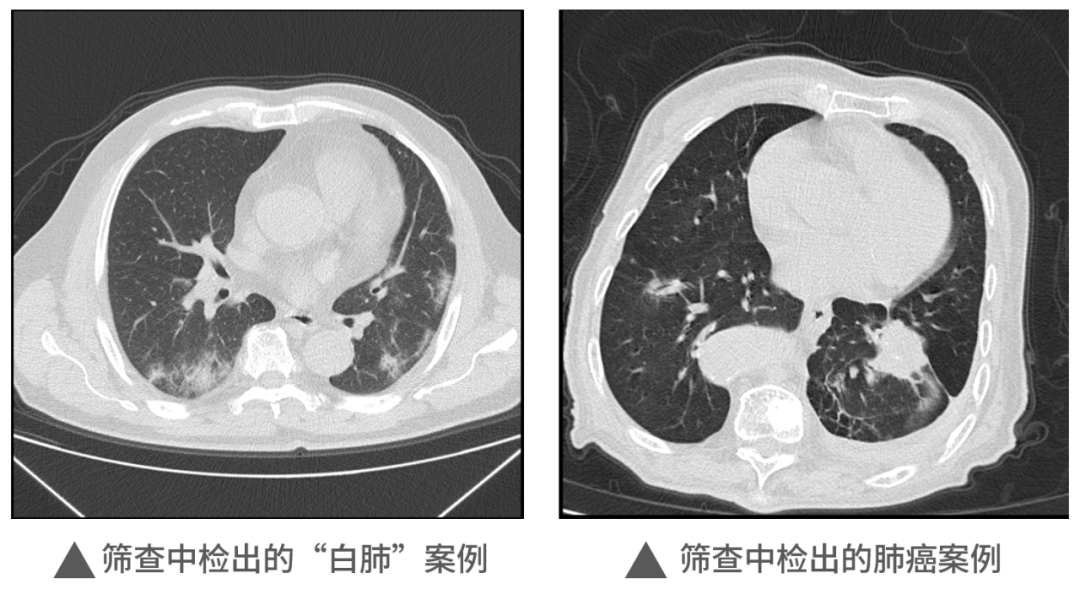

本次活動中,明峰醫(yī)療移動CT充分展現(xiàn)了它的適應性和便利性,在近1000人的檢查中,共查出肺部炎癥300余例,肺部結節(jié)560例,同時檢出一例肺癌病例。這對于本次篩查人員今后胸部健康和治療提供了重要的參考和指導,為全區(qū)居民和企業(yè)提供了堅實的保障,同時大大提升區(qū)內的醫(yī)療健康保障能力。未來,明峰醫(yī)療醫(yī)療仍將持續(xù)致力于高端醫(yī)療設備的普惠應用。作為杭州市錢塘區(qū)的區(qū)內企業(yè),將沿著區(qū)委區(qū)政府“四個全域”建設的發(fā)展規(guī)劃和區(qū)衛(wèi)健系統(tǒng)提出的目標及要求,發(fā)揮人才企業(yè)的優(yōu)勢,以科技創(chuàng)新引領企業(yè)發(fā)展,為區(qū)內產(chǎn)城融合的服務配套做好應有的保障和支撐工作,探索政產(chǎn)學研合作的新思路新模式,共建共享,共同成長,造福更多的人民百姓,在書寫中國式現(xiàn)代化的錢塘答卷上也添上濃墨重彩的一筆。